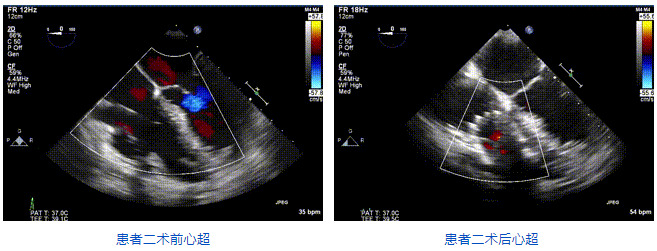

2021年12月24日,復(fù)旦大學(xué)附屬中山醫(yī)院葛均波院士團(tuán)隊成功應(yīng)用LuX-Valve Plus為一例極重度三尖瓣反流(TR)合并房顫、房缺的患者完成了經(jīng)血管三尖瓣置換術(shù),這是在前基礎(chǔ)上,本周完成的第三例經(jīng)血管三尖瓣置換手術(shù),葛均波院士、周達(dá)新教授等與心外科魏來教授、賴顥教授,心超室的潘翠珍教授、李偉教授及麻醉科的郭克芳教授共同完成了本周手術(shù),均獲得圓滿成功!患者術(shù)后超聲顯示無TR,臨床癥狀明顯改善。本周手術(shù)的成功也為LuX-Valve Plus救治性臨床研究添上了濃墨重彩的一筆。

本周三例接受LuX-Valve Plus經(jīng)血管三尖瓣置換術(shù)的患者中,第一例患者為冠狀動脈旁路移植術(shù)+Bentall+二尖瓣成形術(shù)后;第二例患者為永久起搏器植入術(shù)后,存在跨三尖瓣導(dǎo)線;第三例患者合并房顫、房缺及左心耳封堵術(shù)后。

三例患者入院后,葛均波院士團(tuán)隊周達(dá)新教授、潘文志教授、張源博士、陳莎莎博士及心超室的潘翠珍教授、李偉教授對患者的情況進(jìn)行詳細(xì)評估和討論,最終決定為三例患者選擇LuX-Valve Plus40mm、50mm和50mm型號的瓣膜進(jìn)行手術(shù)治療。手術(shù)后即刻拔除氣管插管,術(shù)后患者三尖瓣反流癥狀得到顯著改善,復(fù)查心超結(jié)果顯示人工三尖瓣瓣膜支架固定穩(wěn)定,瓣葉關(guān)閉形態(tài)未見異常,未見明顯反流。